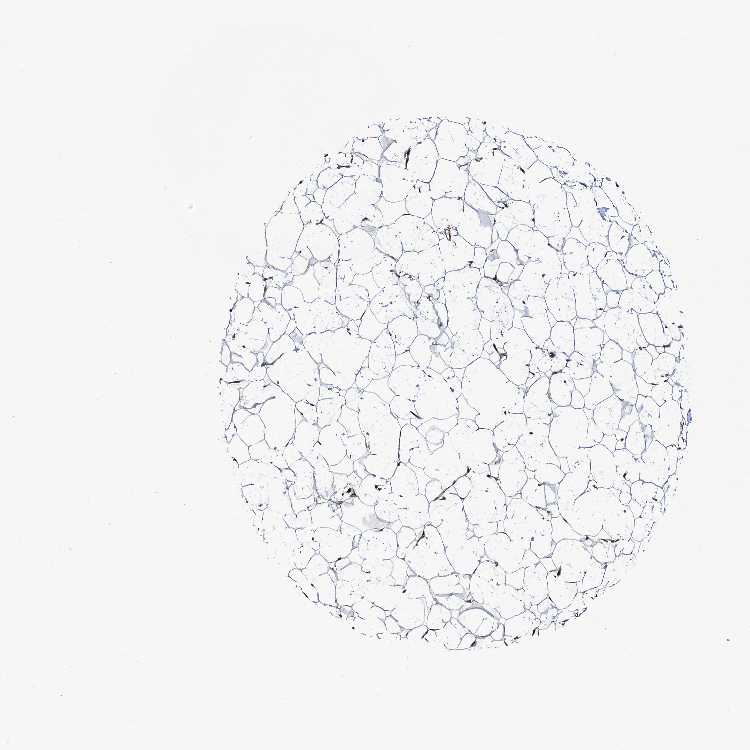

ADIPOSE TISSUE - Antibody stainingi

Antibody staining in the annotated cell types in the current human tissue is reported as not detected, low, medium, or high, based on conventional immunohistochemistry profiling in selected tissues. This score is based on the combination of the staining intensity and fraction of stained cells.

Each image is clickable and will lead to virtual microscopy that enables deeper exploration of all samples and also displays staining intensity scores, fraction scores and subcellular localization as well as patient and tissue information for each sample.

Antibody HPA040410Antibody HPA040441

Adipocytes Not detectedNot detected